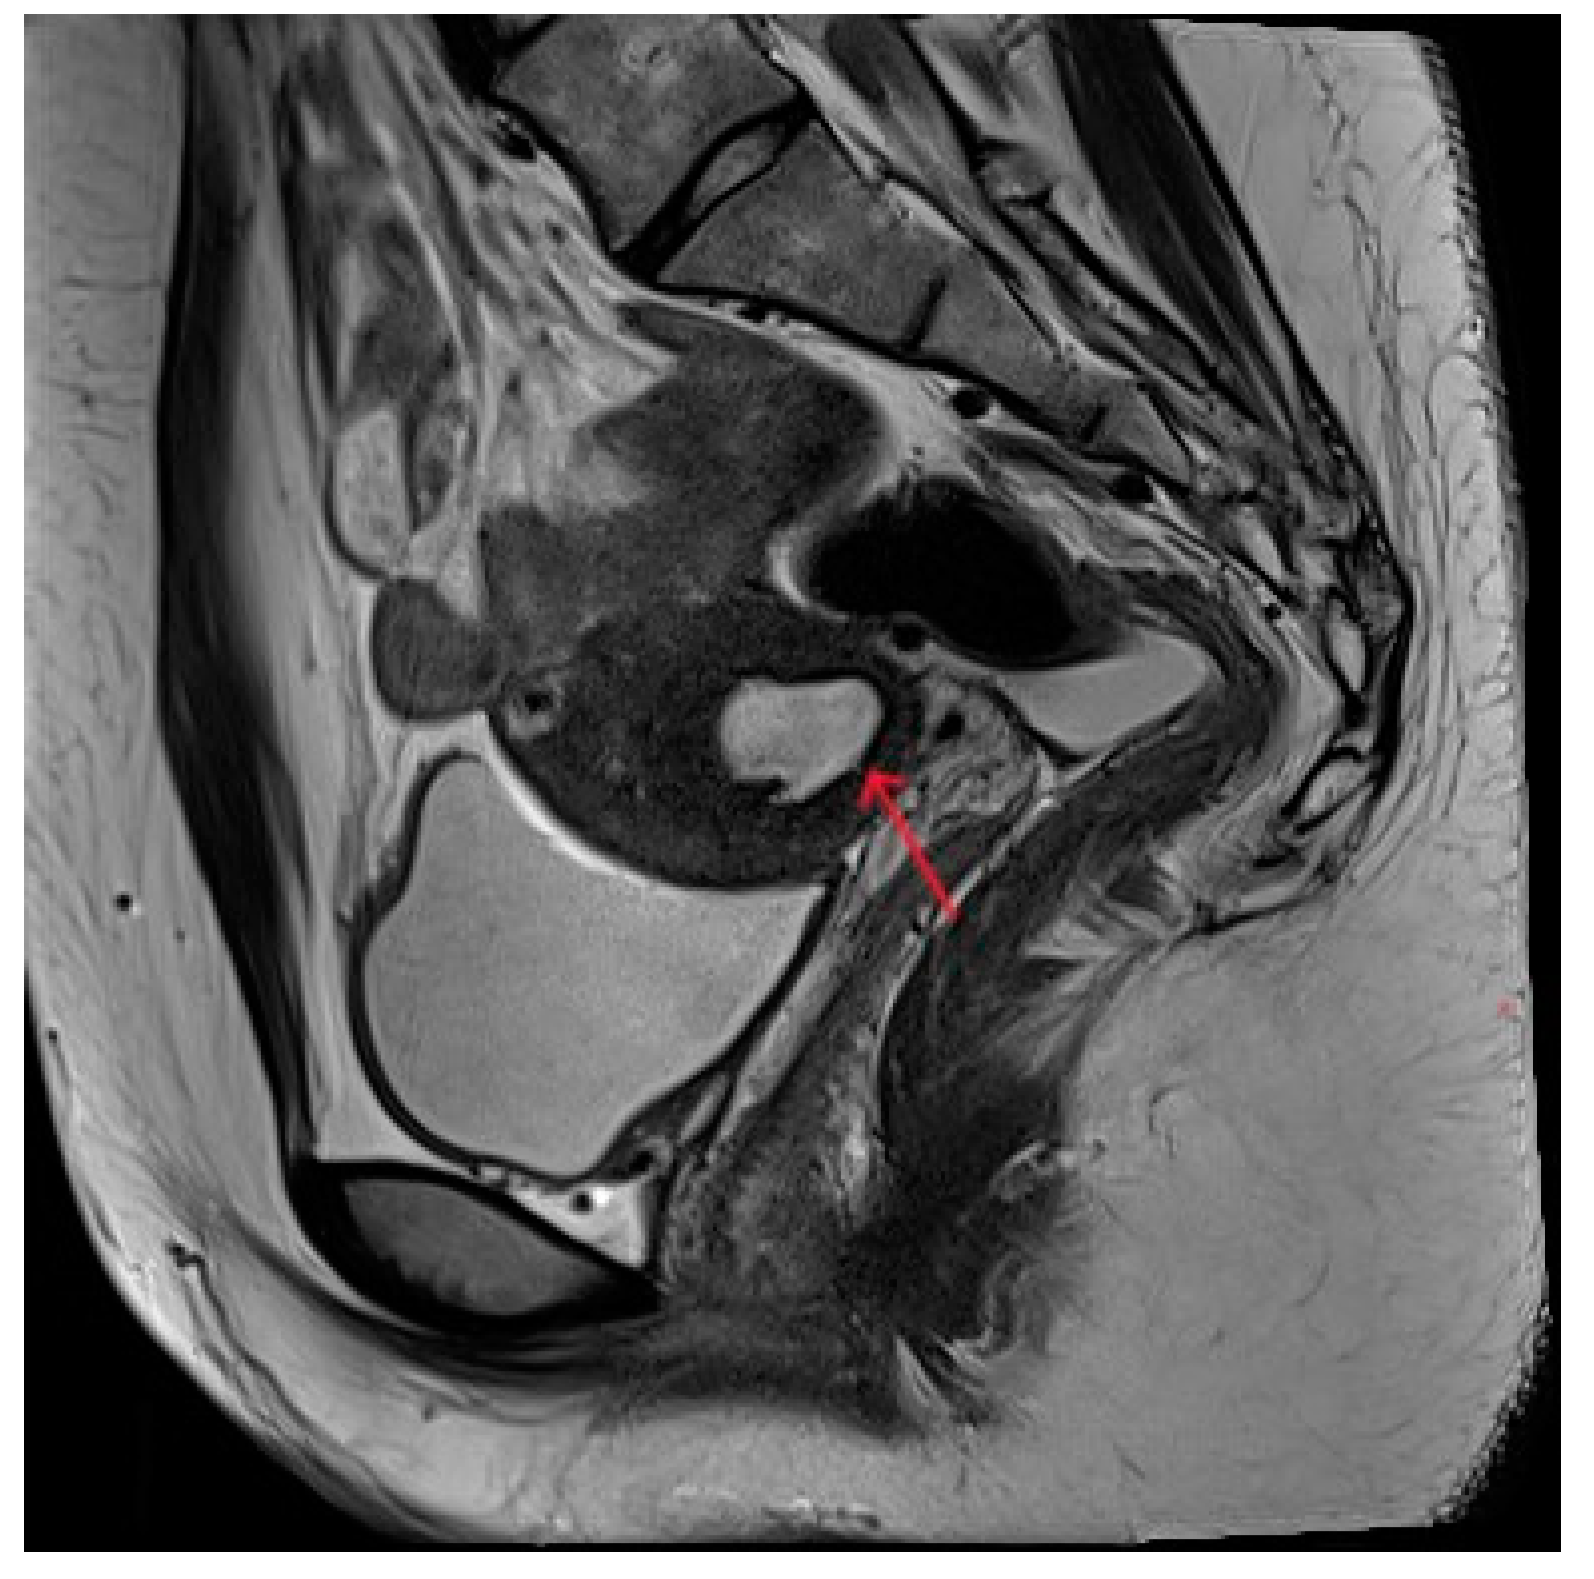

Figure 4.

Pelvic MRI shows lesions after HIFU treatment (5th year) (red arrows).